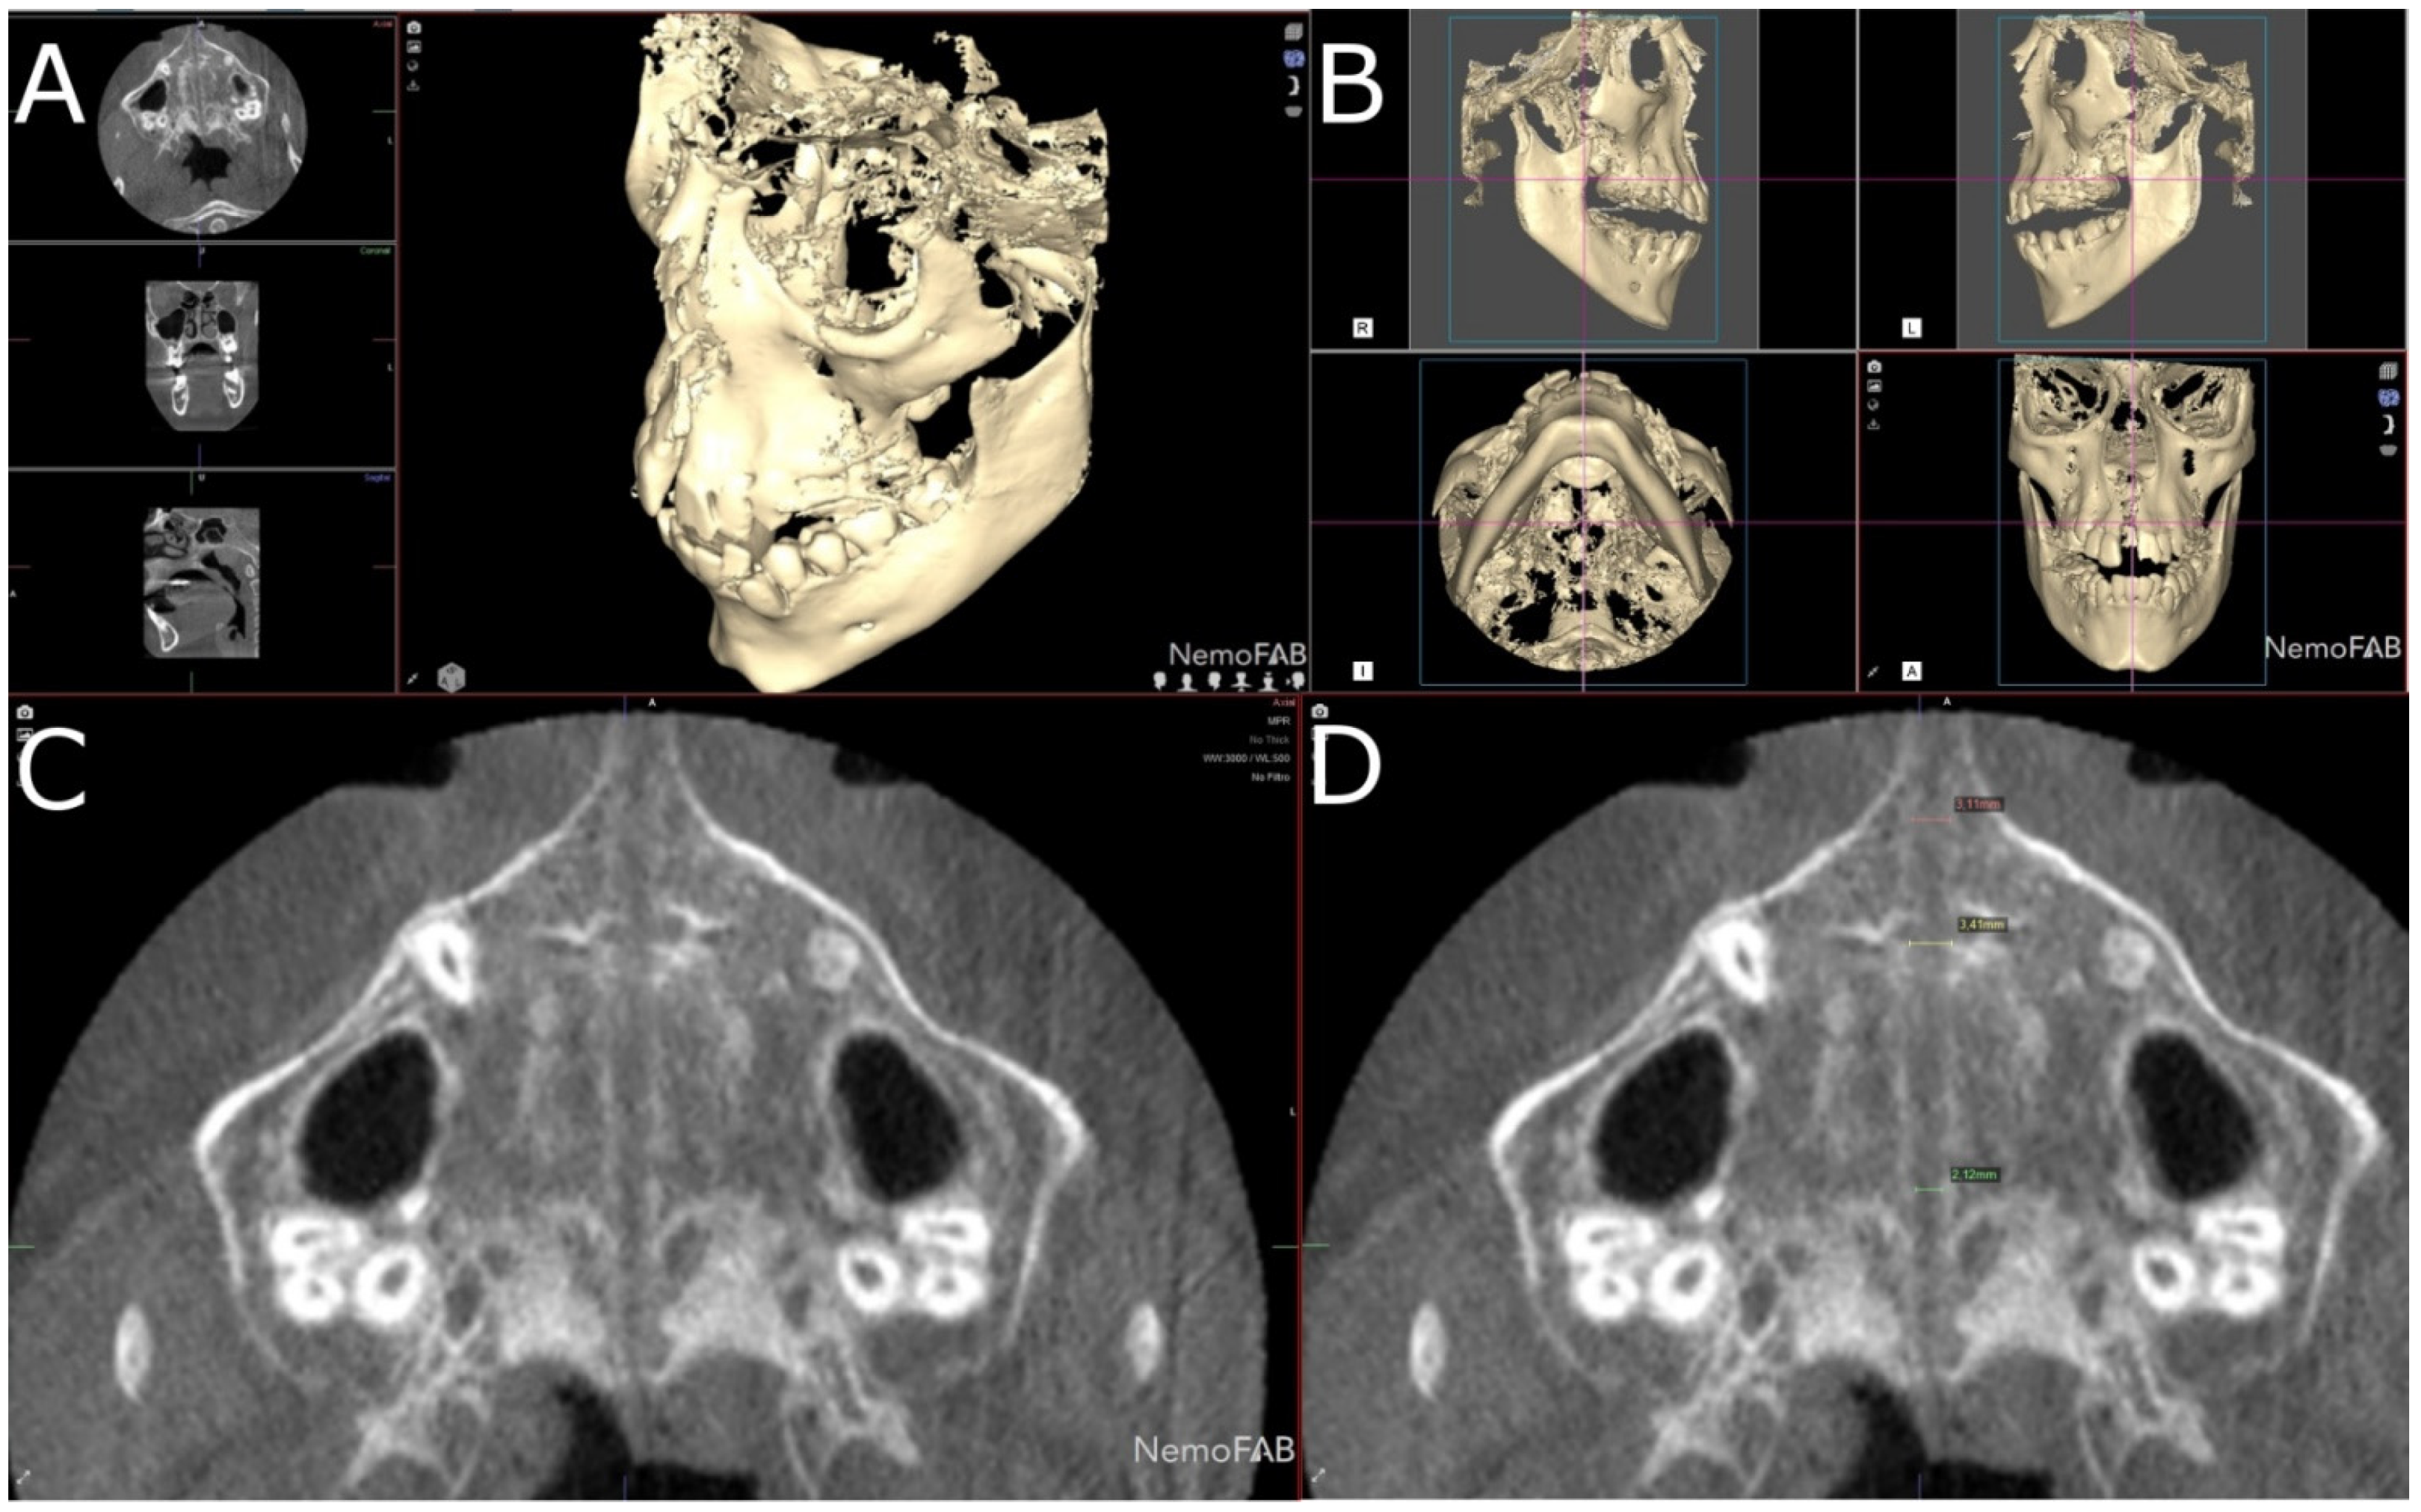

Figure 1.

(A) Preoperative occlusal and (B) frontal view, and (C) postoperative occlusal and (D) frontal view after RME treatment with McNamara appliance.